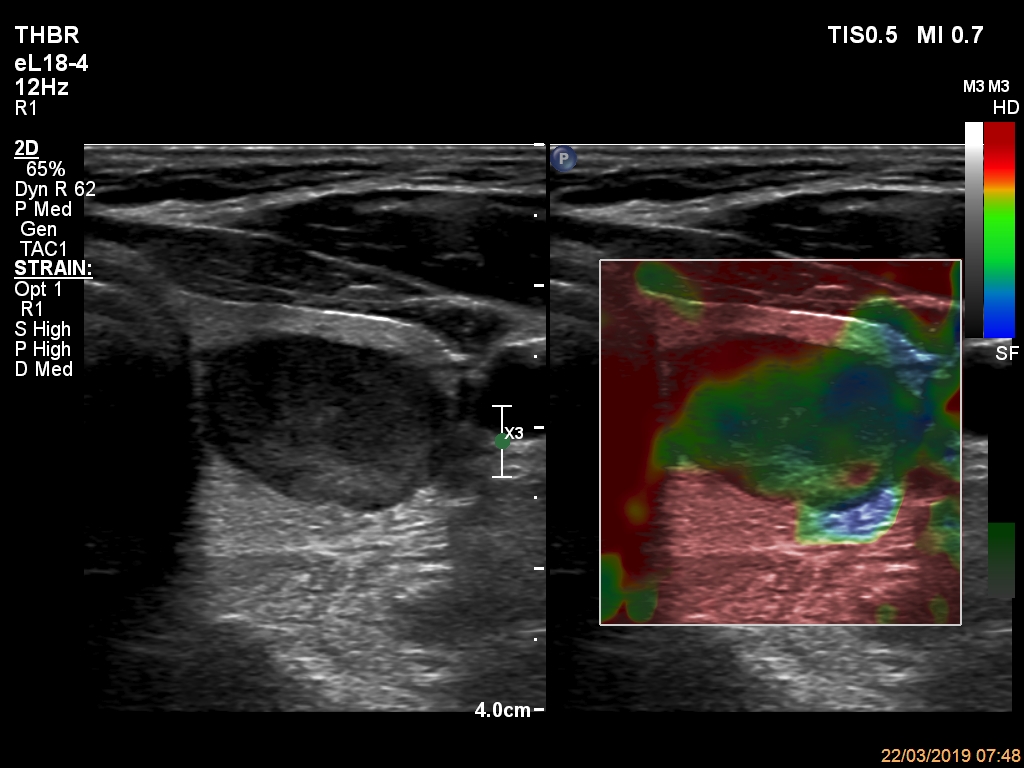

Right lobe, longitudinal scan

Left lobe, transverse scan, elastography. The stiffness of the nodule is average.